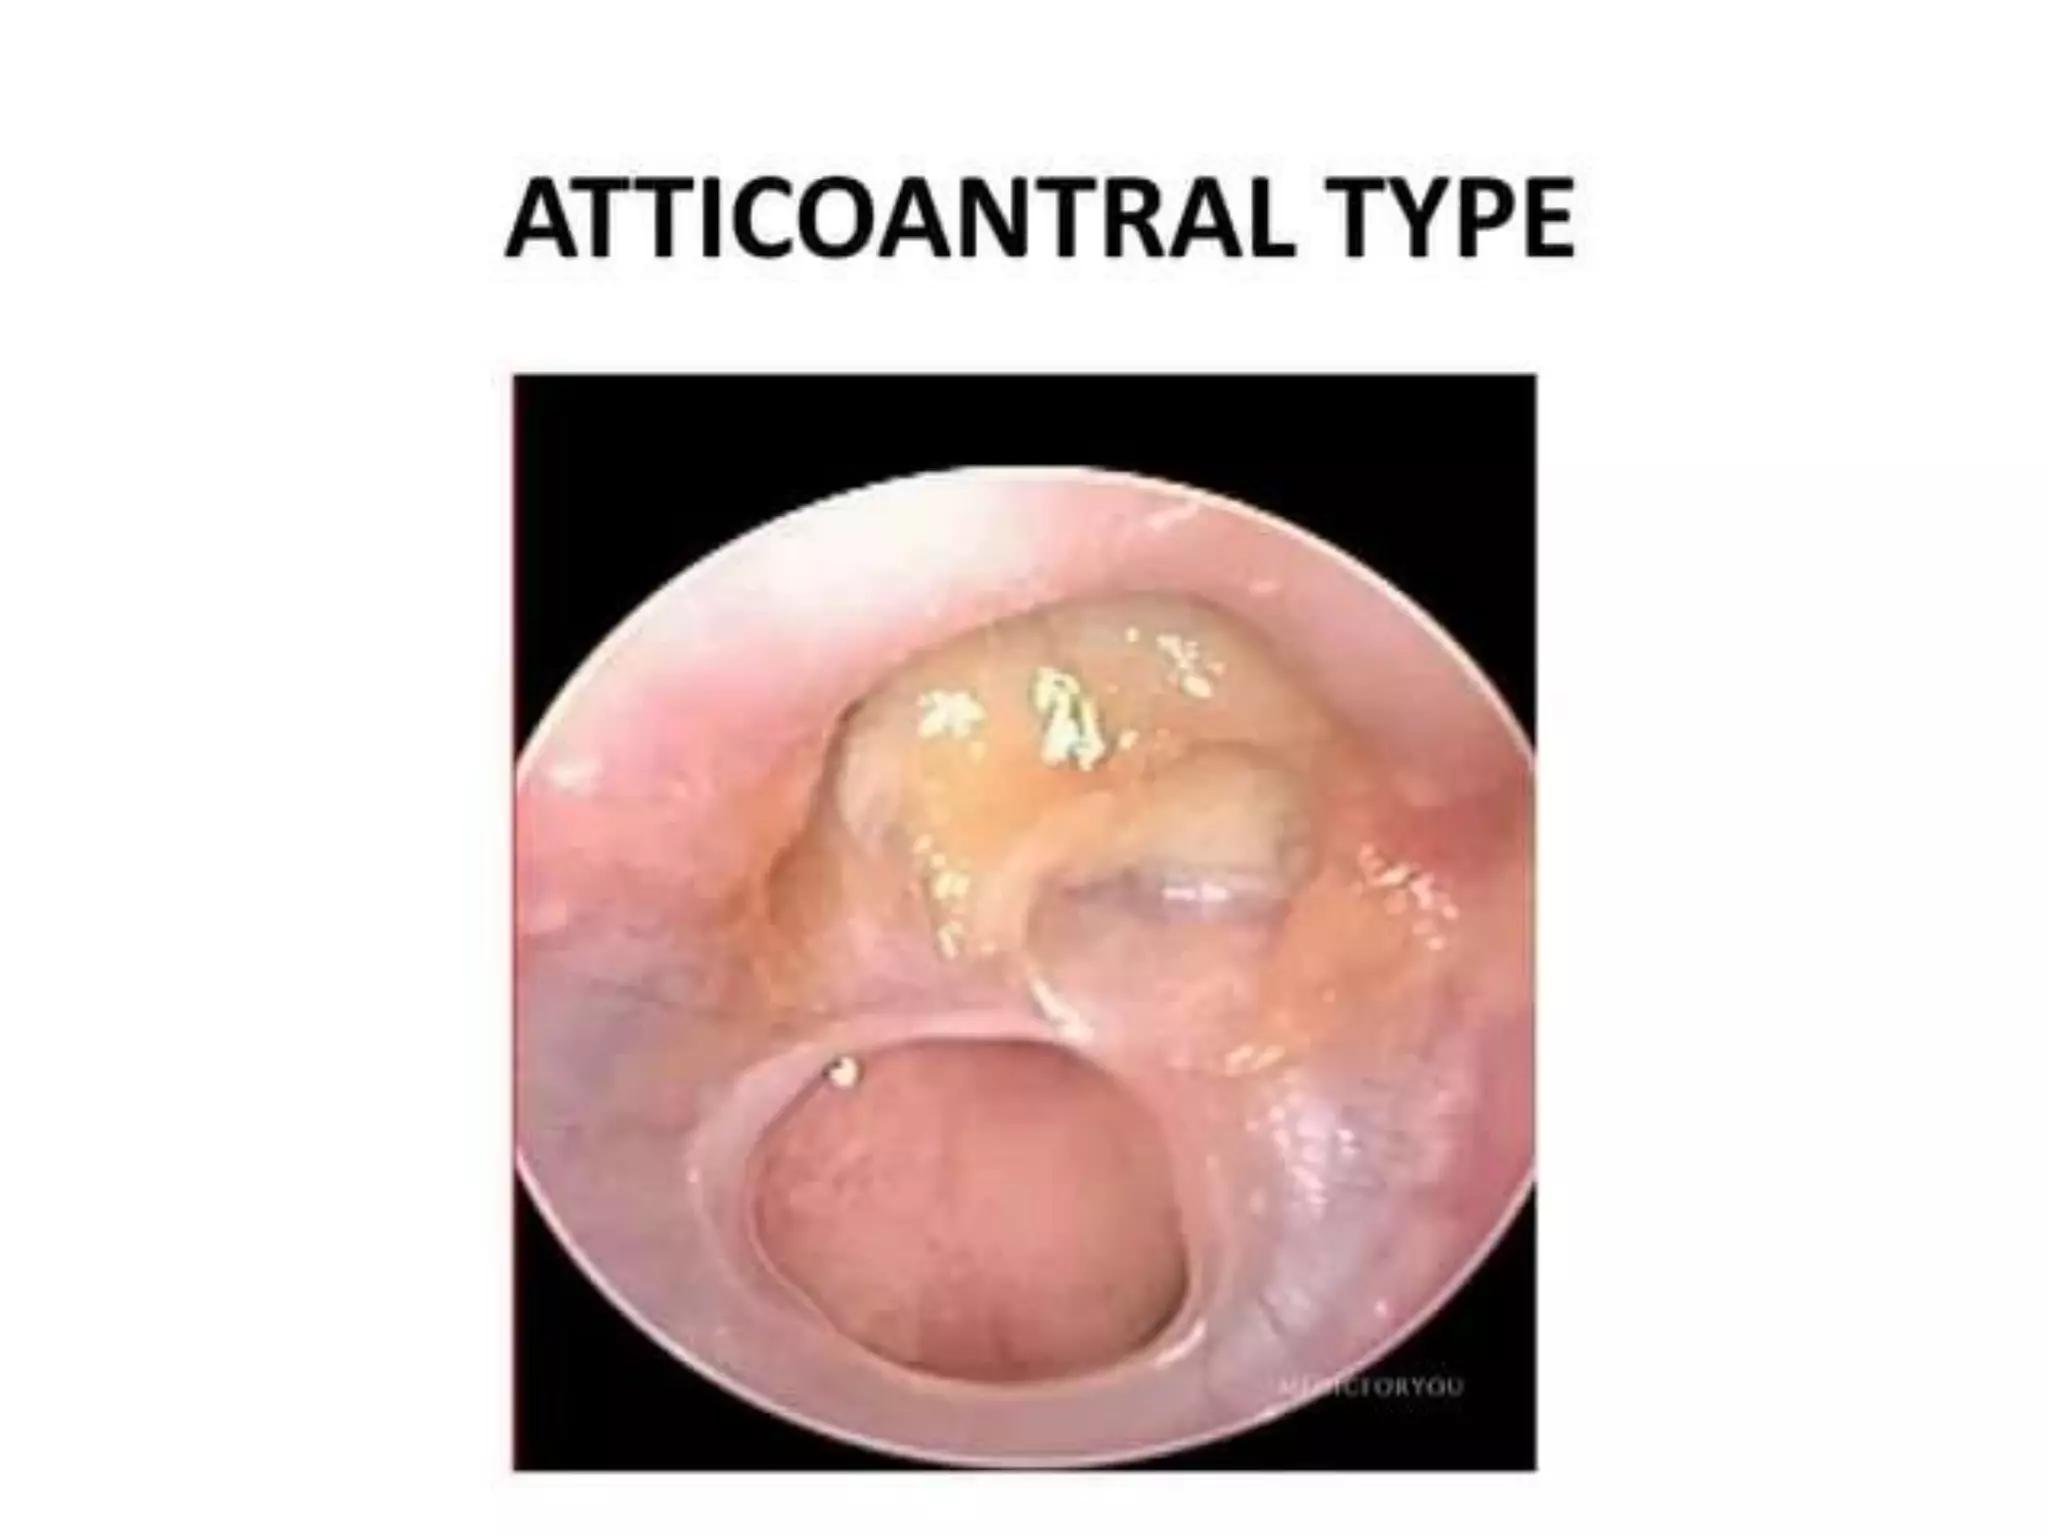

Chronic otitis media is a chronic inflammation of the middle ear and mastoid cavity that presents with recurrent ear discharge through a perforated eardrum. It has several subtypes depending on the state of the eardrum perforation and epithelium. It can be caused by prior acute otitis media, genetics, environment, eustachian tube issues, gastroesophageal reflux disease, craniofacial abnormalities, or immune deficiency.